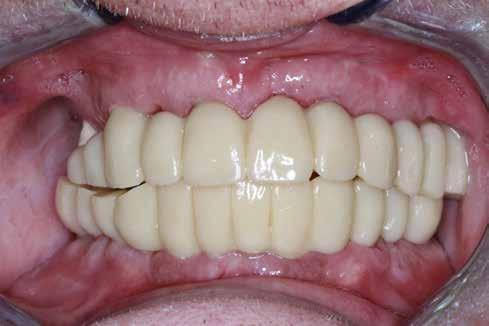

Hagyományos teljes fogsor hatékony átalakítása

Teljes ívű rehabilitáció primer vázra ragasztott lítium-diszilikát szekunder koronákkal